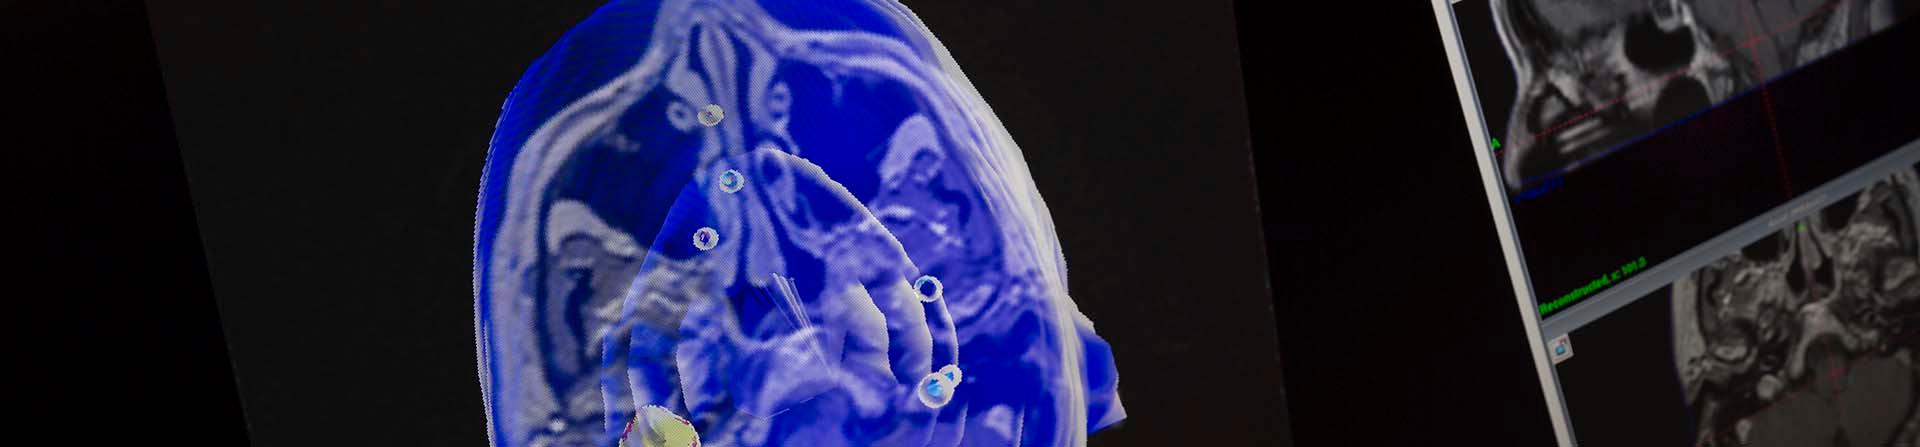

Scan of brain

Getting diagnosed with a brain tumor brings lots of questions and uncertainty. A benign brain tumor, or non-cancerous brain tumor, can affect you in a number of ways. You might be having headaches or problems balancing, swallowing, or speaking.